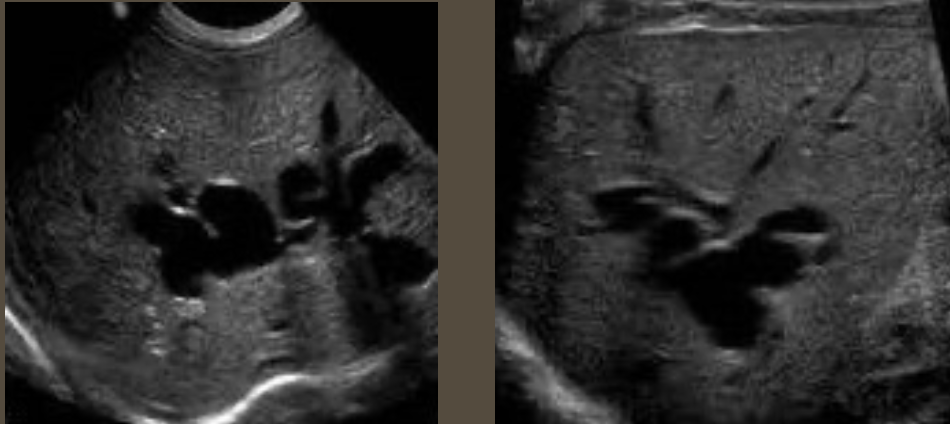

2D US: pancreas enlargement, hypoechoic parenchyma from edema, irregular ill-defined borders, peripancreatic free fluid, peripancreatic echogenic inflammatory fat, can have focal areas of inflammation/hypoechoic tissue

2D US: mixed pattern of echogenicity (hyperechoic from fibrosis to hypoechoic from inflammation), calcifications, normal to atrophic size, nodular surface, dilated/calcified pancreatic duct (> 3 mm), solid mass, thrombosis of splenic and portal vein